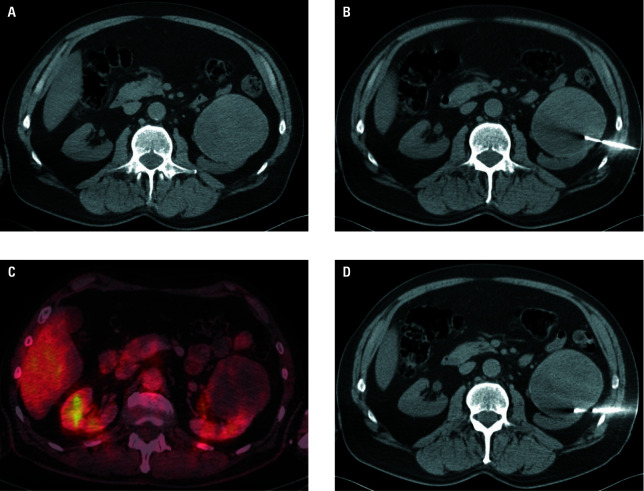

Materials and methods: A total of 138 percutaneous biopsies for tumors ranging from 21 to 133 mm in diameter (median, 72 mm) were carried out in 134 patients with suspected mRCC over a 5‑year period. The biopsy location was variable, with kidney biopsy performed in 77 cases (55.8%), and other localizations (retroperitoneum, peritoneal cavity, liver, pelvis, pleural space, lung, mediastinum, chest or abdominal wall, and pancreas) in 61 cases (44.2%).

Results: As many as 288 biopsies (97.1%), yielded truepositive results, and 4 procedures (2.9%) yielded histologically falsenegative results that required confirmation through extended rebiopsy. RCC was the most common individual diagnosis (85.5%), with non‑RCC histology verified in 14.5% of cases. In total, 32 complications (23.2%) were confirmed, 2 of which were pneumothoraces, 29 were minor bleeding that needed only conservative management, and 1 case required angiography and embolization for hemorrhage treatment. While no significant relationship between the biopsy success and lesion localization (renal vs other) was found (P = 0.13), the relationship between complication rate and biopsy localization (renal vs other) was significant (P = 0.01).

Abstract Image